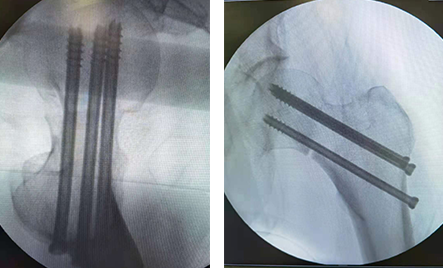

术中

术中透视正位(左图)术中透视侧位(右图)

“天玑”拥有的“透视眼”,让手术实现微创,不再需要开大刀,剥离皮肤、肌肉、神经!一台左股骨颈骨折复位内固术,不到40分钟,即可顺利完成。

术后伤口仅有1厘米

创伤骨科任海东主任说,以往股骨颈骨折如何精准置钉一直是个难题,但在机器人导航辅助下,手术团队将精确度误差控制在0.2毫米以内。整个手术过程中,透视次数大幅减少,对患者及医护人员的放射保护大大增强。而且创口仅1厘米,患者术后几乎感觉不到疼痛。